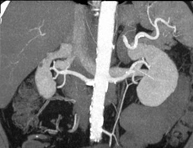

Prova diagnòstica no invasiva que consisteix en l'estudi de l'artèria aorta abdominal a través de l'obtenció d'imatges d'alta definició anatòmica mitjançant l'ús d'un equip de TC (Tomografia Computeritzada) i de contrast iodat. La qualitat de les imatges permet realitzar reconstruccions en 2D i 3D gràcies a estacions de treball especialitzades en l'estudi arterial. Està indicat en aquells pacients amb malaltia vascular (arteriosclerosi), en aneurismes d'aorta, en pacients amb dolor abdominal de possible origen vascular, en estudis prequirúrgics de lesions adjacents a l'aorta abdominal com a "mapa" vascular. La informació obtinguda de manera no invasiva és indispensable per als pacients que requereixen tractament percutani o quirúrgic. En aquells pacients que només requereixen seguiment de les lesions vasculars, aquesta tècnica és la tècnica no invasiva d'elecció juntament amb l'angio-RM. - Angio-TC Artèries renals

Prova diagnòstica no invasiva que consisteix en l'estudi de les artèries renals a través de l'obtenció d'imatges d'alta definició anatòmica mitjançant l'ús d'un equip de TC (Tomografia Computeritzada) i de contrast iodat. La qualitat de les imatges permet realitzar reconstruccions en 2D i 3D gràcies a estacions de treball especialitzades en l'estudi arterial. Està indicat en aquells pacients amb malaltia vascular (arteriosclerosi), en aneurismes d'aorta, en pacients amb dolor abdominal de possible origen vascular, en estudis prequirúrgics de lesions adjacents a l'aorta abdominal com a "mapa" vascular. La informació obtinguda de manera no invasiva és indispensable per als pacients que requereixen tractament percutani o quirúrgic. En aquells pacients que només requereixen seguiment de les lesions vasculars, aquesta tècnica és la tècnica no invasiva d'elecció juntament amb l'angio-RM. - Angio-TC Aorto-ilíac